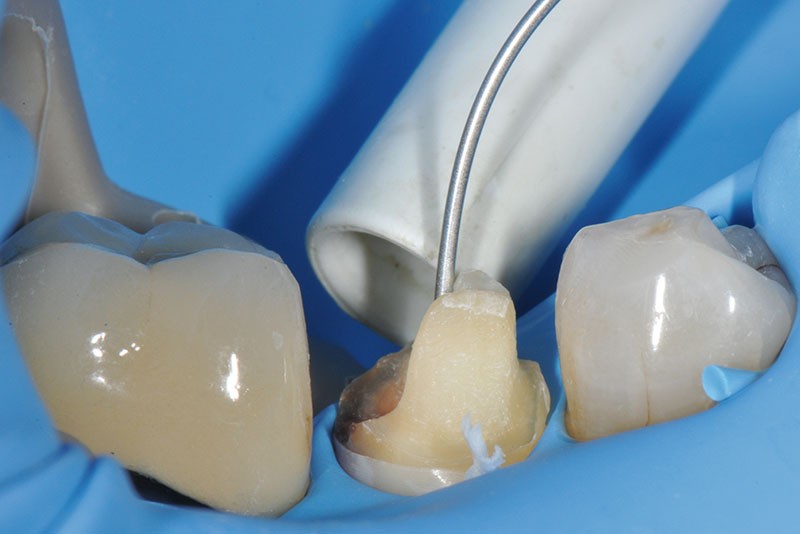

7, 8, 9. L’obturation canalaire à la gutta percha est partiellement éliminée avec le foret universel et le canal radiculaire est mis en forme avec le foret de calibrage 3M™ RelyX™ Fiber Post de 1,1 mm de diamètre. L’élimination totale de la gutta percha sur la longueur désirée est vérifiée à l’aide d’une radiographie rétro-alvéolaire. Un insert à ultrason est utilisé, son action mécanique permettant de finir de nettoyer le système canalaire et d’éliminer les résidus de ciment endodontique pouvant encore être présents.